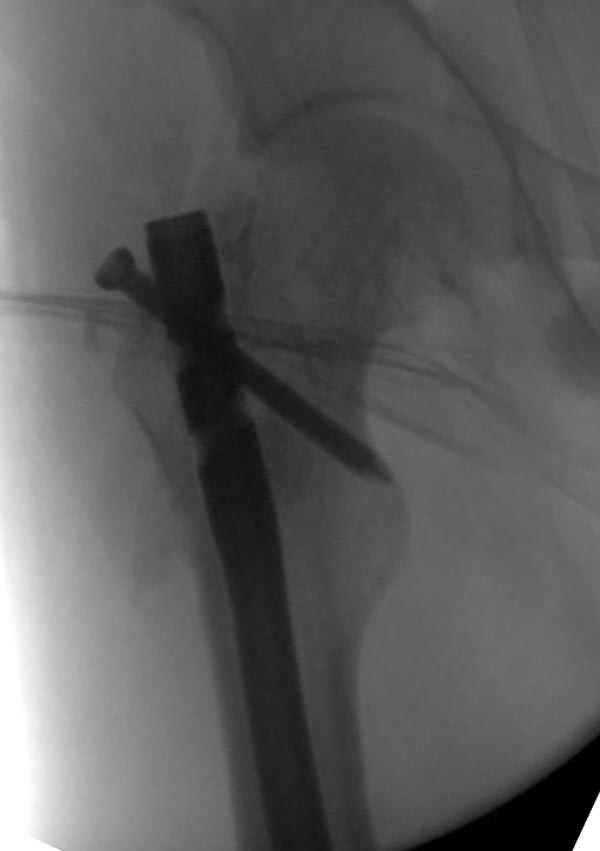

Рутинный интрамедуллярный остеосинтез с расверливанием и с фиксацией реконструктивным трокантерик штифтом (рис №1, №2),

если первые 4 месяца послеоперационного периода проходил без проблем, но на 5 месяце появились боли в дистальном отделе бедра и температура, т.е. симптомы медуллярного инфицирования (рис №3, №4).

При обзоре причин перелома, на снимке №2 обнаружили, что один из стержней аппарата наружной фиксации проходил только через передний кортекальный слой, что создало стрессовую зону на бедре и в результате перелом из-за незначительной травмы.

На снимке N2 виден канал от стержня во фронтальной плоскости, на уровне которого на снимке N7 уже перелом.